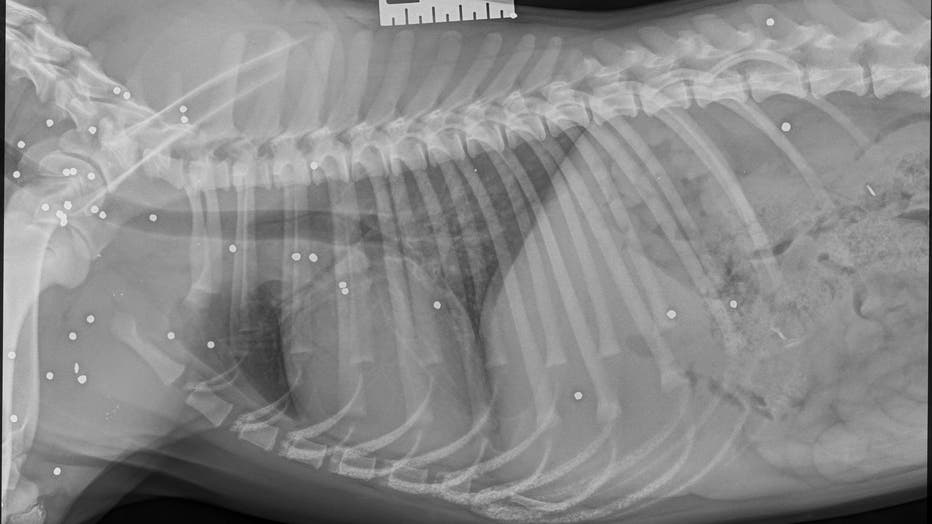

"Upon examination, SAHS veterinarians believed Tammi was hit by a car and was shot with a shotgun. Her X-rays revealed more than 70 shotgun pellets in her body," they wrote on Facebook.

The pup underwent surgery to repair her pelvis and restore her mobility. She was then sent to a foster home for recovery.